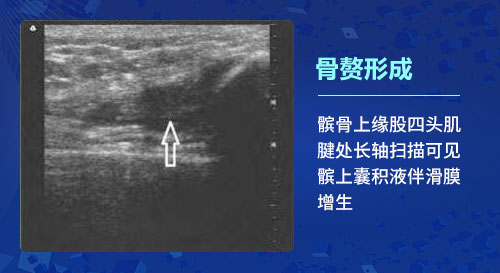

二、骨赘形成:随着骨关节炎的病情进展,骨关节炎患者的软骨退变通常软骨内会伴随骨化形成的骨赘,如果骨赘比较大,则可能影响骨关节的正常活动,甚至脱落在髌上囊或关节腔内而导致游离体形成。关节病变还会刺激邻近组织和滑膜,导致滑膜增生及炎性渗出。肌骨超声技术可观测到关节边缘出现不规则的强回声突出,判断患者病变部位是否存在滑膜肥大、增生,越是严重的滑膜增厚,显示出彩色的血流信号也就会越丰富。